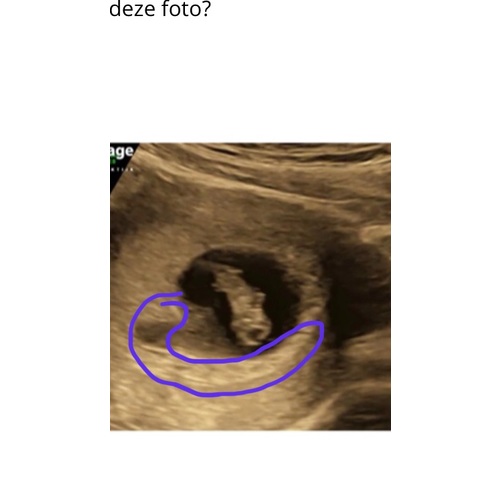

Hier is hij !

Inwendig 馃挅

Uitwendig 馃挋

Heeft te maken met spiegelbeeld in of uitwendig xxx